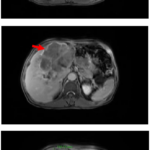

Case lâm sàng: Điều trị miễn dịch kết hợp thuốc kháng tăng sinh mạch cho bệnh nhân ung thư biểu mô tế bào gan tại trung tâm y học hạt nhân và ung bướu – BV Bạch Mai

Case lâm sàng: Điều trị miễn dịch kết hợp thuốc kháng tăng sinh mạch cho bệnh nhân ung thư biểu...